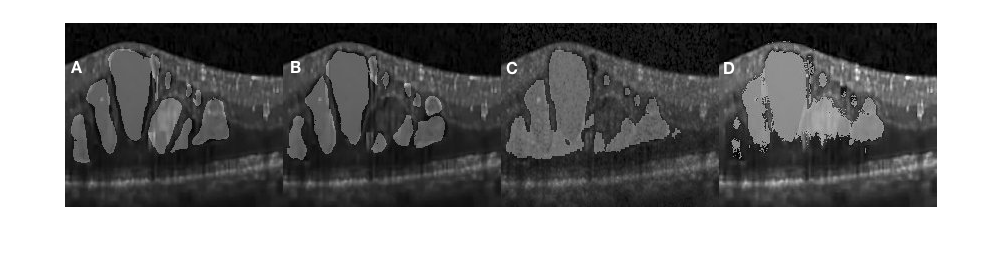

In Fig. 4.3 (D) we demonstrate results of our framework operating on images depicting more severe morphological conditions. The retinal layer in Fig. 4.3 (A) was destroyed by a large section of edema which mixed various shapes of fluid and concrete edemas. The central fluid section is fused with the concrete part on both the left and the right-hand side of the images, where both sections were successfully segmented by our approach. It can be seen that our approach shows that the segmentation achieved is consistent with the appearance of the pathology and accurately covers the entire region. Several small sections were also well segmented but some slimmer region is not detected since it is too slim to be perceived by the network. In Fig. 4.5, we present additional results from severe conditions that present complex structure appearances.

Figure 4.5 depicts the comparison of our method with the one reported in Chiu et al. [19] for three segmentation attempts carried out complex retinopathy conditions. It is found that Chiu’s method performs a slight over-segmentation near the bottom area. The segmentation results carried out with our method are closer to those which have been manually segmented. In Fig. 4.6, three images are shown which depict segmentation results on concrete and non-obvious fluid edema. The over-segmentation noted earlier can also be observed , as well as a false segmentation happening in the region on the left-hand side. Again, the results obtained with our method have a better agreement with those obtained via manual segmentation. Furthermore, our results are more adherent to target based on image content. This is also found in Fig. 4.7 where additional results are presented from the segmentation of an example of fluid edema. Quantitatively, we compared the Dice overlap coefficient and -value of Wilcoxon matched-pairs test for the DME region. Dice coefficients were calculated for all 10 patients and the process was repeated as per[19]. Specifically, the Dice coefficient was calculated based on all test images and the Wilcoxon matched-pairs test was calculated based on the mean Dice coefficient across all patients for our automated method and for the corresponding results from two graders. It was found that the Dice coefficient of our approach is standing for mean and standard deviation which outperforms reported in [19] (the higher, the better). Both methods are comparable with the Dice coefficient between manual graders ( ). The -value for our approach is , which is also better than reported in Chiu et al. [19] (where a coefficient value of indicates perfect agreement).